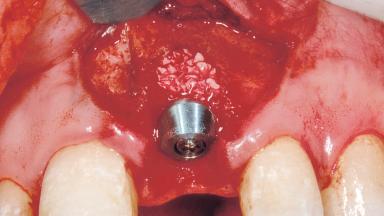

A 33-year-old female patient presented with an upper left central incisor that required extraction after a failed endodontic therapy. The tooth had been traumatized when the patient was a teenager and had undergone several endodontic treatments, including two apicectomy procedures. The patient was in good health and did not smoke. Clinical examination showed that the patient had a high lip line. In full smile, the gingival margins of the upper teeth were visible to the first molars. The gingival margins of central incisors 11 and 21 were only just showing. Examination of tooth 21 confirmed that the tooth was mobile and had hypererupted by 1 mm.

Bone Augmentation Horizontal|Simultaneous

Augmentation Materials Xenogenous|Membrane

Placement Protocol Immediate implant placement

Socket Integrity Damage to one or more bone walls

Bone Volume Damage to one or more socket walls